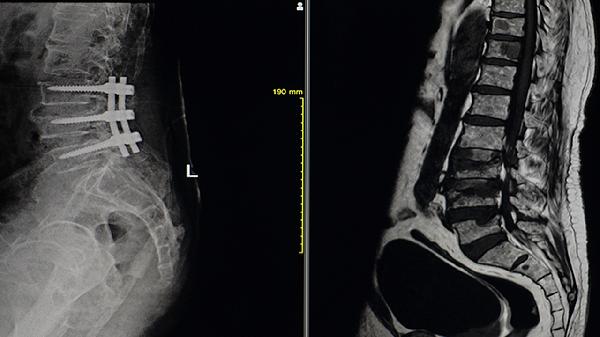

3、手术治疗

如果病情较为严重,甚至出现关节畸形,可能需要考虑手术治疗。例如,全髋关节置换术或截骨矫形术可以纠正畸形,改善功能。